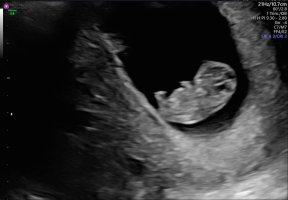

Det viktigste er at alt sto bra til. Målt en dag lengre fram, men siden dette er ivf så kan ikke dato endres etter størrelse

Nå kan denne overnervøse mammaen roe seg litt ned igjen

Vis vedlegget 438550